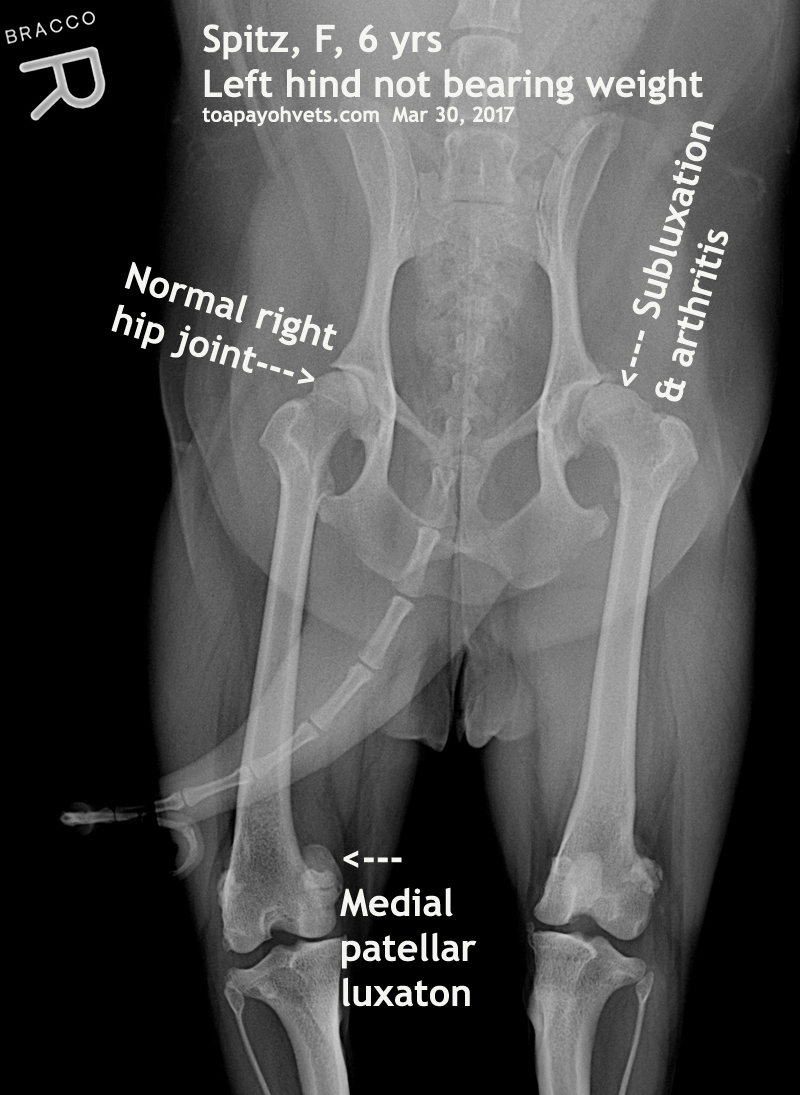

From 2010vets.blogspot.com

Veterinary, Photography and Travel Stories for vet students and pet Can A Cat Walk On A Dislocated Hip If your cat has a dislocated joint, it needs to be looked by a veterinarian in order to get a proper diagnosis and treatment. When the round ligament of the hip joint in a cat ruptures or stretches out, the top of the femur can dislocate from the socket of the pelvis. While some cats may spontaneously heal from a. Can A Cat Walk On A Dislocated Hip.

From www.sinpets.com

veterinary medicine, surgery, singapore, toa payoh vets, dogs, cats Can A Cat Walk On A Dislocated Hip Your veterinarian will be able to do testing to assess the extent of the dislocation and then should start treatment so that your cat regains its mobility. Subluxation refers to dislocation with no damage to these surrounding parts. When the round ligament of the hip joint in a cat ruptures or stretches out, the top of the femur can dislocate. Can A Cat Walk On A Dislocated Hip.